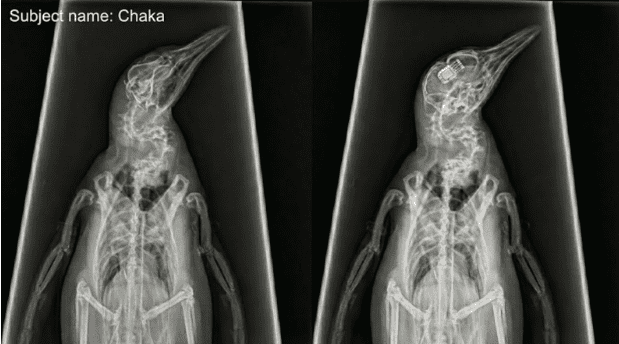

In a hastily assembled livestream on X (formerly Twitter) that began late Wednesday evening, Neuralink founder Elon Musk announced a pivotal shift in the company’s operational roadmap. Moving beyond their publicized trials with swine and macaques, the company has successfully implanted a modified N1 neural device into an avian subject: a four-year-old fairy penguin named Chaka.

According to Dr. Patel, Chaka received the “N1-A” (Avian variant), a miniaturized version of the standard implant with thinner, more flexible electrode threads designed to navigate the denser neural topography of a bird’s skull without causing tissue damage during high-speed swimming maneuvers. The surgery took six hours and involved robotic insertion of 512 electrodes.